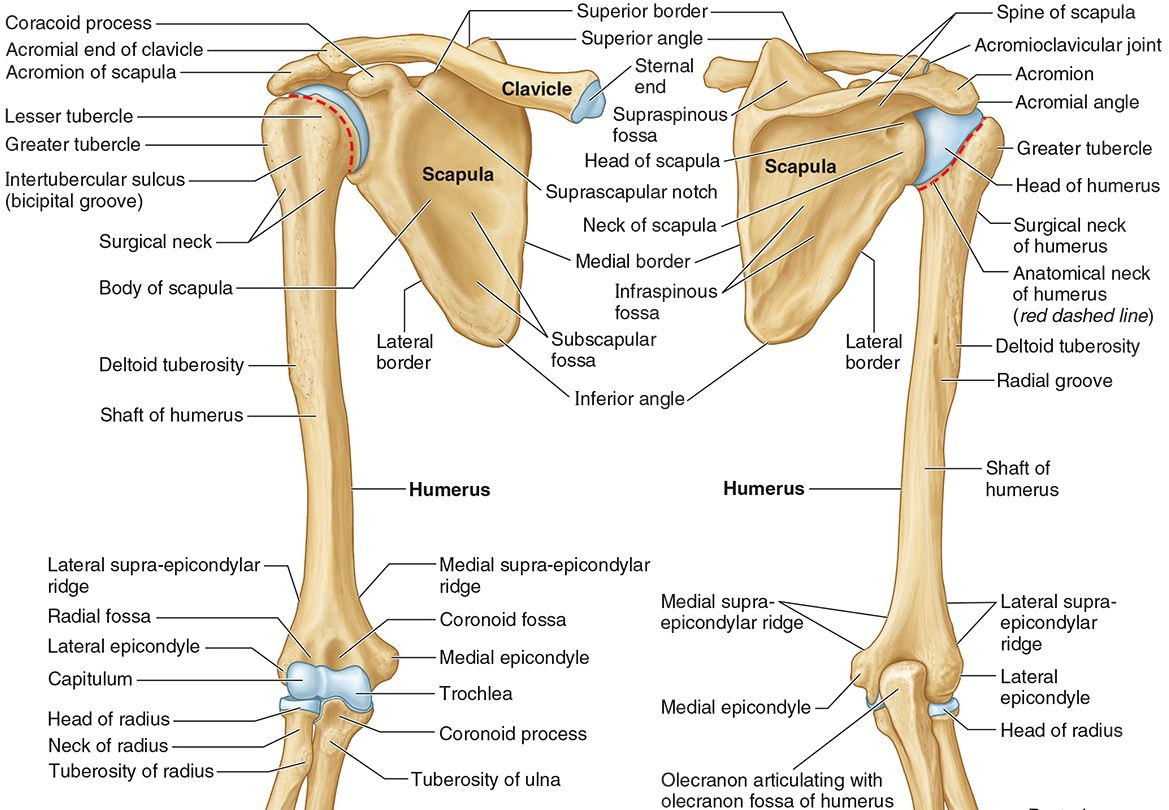

What is the only bone in the upper arm?

The humerus

What part of the humerus is this?

The head of the humerus articulates with the scapula at the glenohumeral joint.

What part of the humerus is this?

The anatomic neck is an indentation distal to the head and provides an attachment for the fibrous joint capsule of the glenohumeral joint.

What part of the humerus is this?

The greater tubercle lies lateral and distal to the anatomic neck.

What part of the humerus is this?

The lesser tubercle lies on the anterior/medial side of the humerus, just distal the anatomic neck.

What part of the humerus is this?

The intertubercular (bicipital) groove lies between the greater and lesser tubercles.

What part of the humerus is this?

The surgical neck is a narrow area distal to the tubercles. It is a common site for proximal humerus fractures.

What part of the humerus is this?

The humeral shaft features the deltoid tuberosity laterally for the distal insertion of the deltoid muscle.

What part of the humerus is this?

The radial groove is an oblique depression that contains the radial nerve and deep brachial artery.

Which parts of the humerus is this?

The medial and lateral epicondyles are distal prominences to which many forearm tendons attach, near the elbow joint.

Which parts of the humerus is this?

The medial and lateral supracondylar ridges extend superiorly from the medial and lateral epicondyles.

Which parts of the humerus is this?

The trochlea and the capitulum (the condyles) are the most distal surfaces of the humerus, where it articulates with the forearm bones at the elbow joint

What part of the humerus is this?

The olecranon fossa is a posterior depression above the trochlea that receives that olecranon process of the ulna

What part of the humerus is this?

The coronoid fossa is an anterior depression above the trochlea that receives that coronoid process of the ulna.

What nerve and vascular injuries are associated with Midshaft humerus fracture?

Radial nerve (N.) & deep brachial artery (A.)

What nerve and vascular injuries are associated with Surgical neck humerus fracture?

Axillary N. & posterior humeral circumflex A.

What nerve injury is associated with Supracondylar humerus fracture?

Median N.

What nerve injury is associated with Medial epicondylar fracture?

Ulnar N.

What nerve injury is associated with Lateral epicondyle fracture?

Radial N.